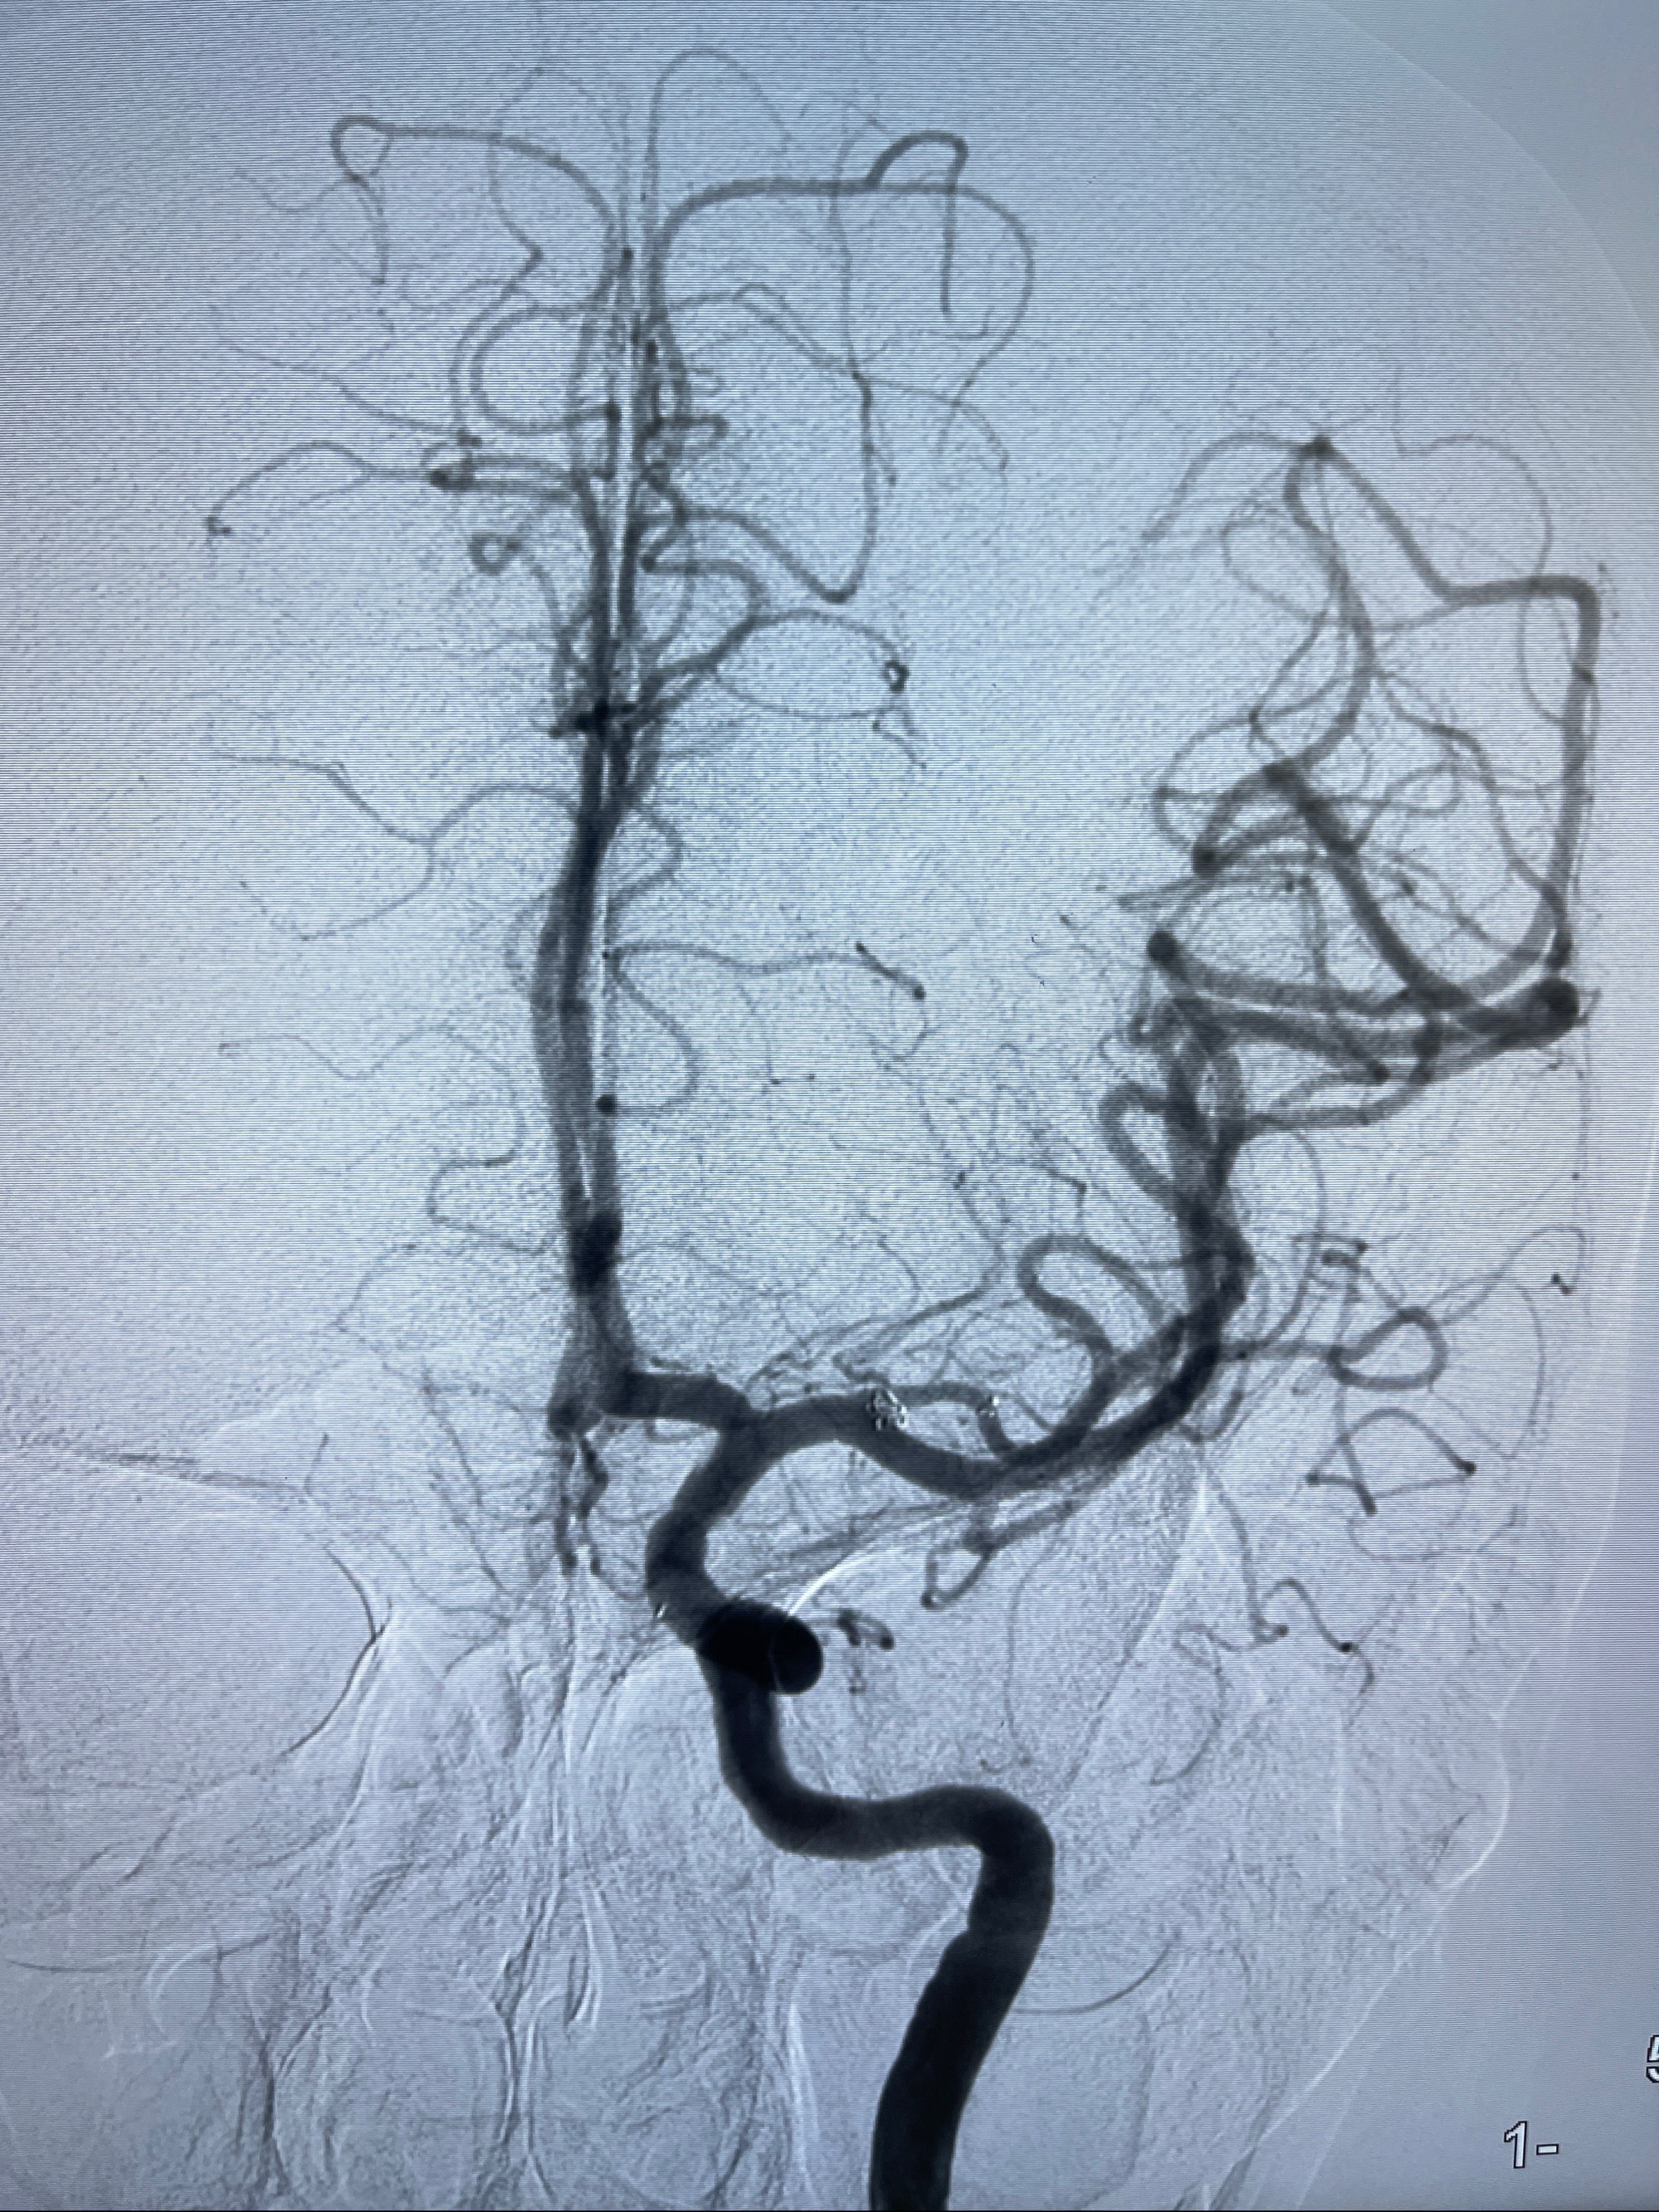

2023-08-14DSA:

左侧大脑中动脉动脉瘤,约2.6-2.8-3.4-2mm大小(瘤颈部、瘤体部、瘤高)

2.外科手术夹闭or介入支架辅助栓塞